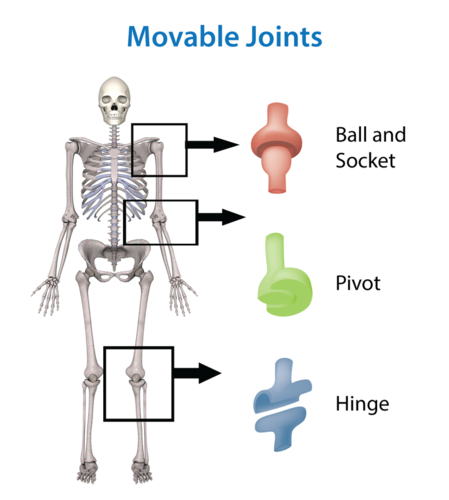

TYPES OF JOINTS

1. The Immovable Joints:

These joints do not allow for movement. These are:

(a) Ball and socket joint:

(b) Gliding joint:

These are found in the limbs. Ball and socket joints are in the shoulder and hip. They allow for movement in more than one plane.

2. The Moveable Joints:

(a) Hinge joint: this is a joint which allows for movement in only one plane/direction e.g. elbow joint.

Gliding joints allows the sliding, twisting or turning of one bone over another e.g. joints at the wrist.

TYPES OF JOINTS

1. The Immovable Joints:

These joints do not allow for movement. These are:

(a) Ball and socket joint:

(b) Gliding joint:

These are found in the limbs. Ball and socket joints are in the shoulder and hip. They allow for movement in more than one plane.

2. The Moveable Joints:

(a) Hinge joint: this is a joint which allows for movement in only one plane/direction e.g. elbow joint.

Gliding joints allows the sliding, twisting or turning of one bone over another e.g. joints at the wrist.